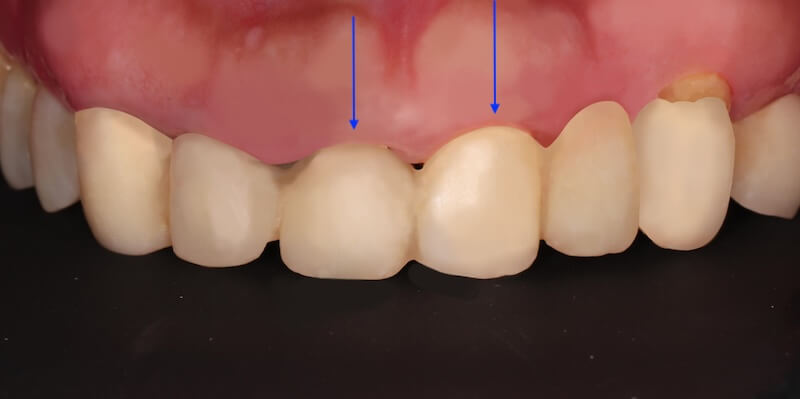

經過第一階段的療程後,我們持續追蹤 Ms.H 刷牙的情況,並且在大約兩個月後追蹤整體復原的進度,我們可以看到牙齦腫大的狀況明顯改善了許多,消腫以後產生了不少縫隙:

經過第二組臨時假牙的配戴,我的建議會是有兩處牙周相關的問題可以做改正:

- 原本兩顆正中門牙的長度並不一致,我們可以利用水雷射進行牙冠增長術。以不開刀的方式雕塑牙齦和內部的齒槽骨,也不需要縫合。讓兩顆正中門牙盡量達到視覺上長度一致。